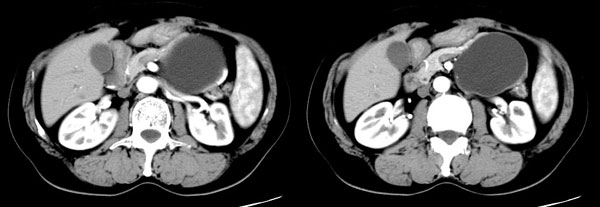

女性,58岁。卵巢癌术后4年余,无不适。体检b超发现左上腹肿块。

ct平扫加增强扫描:胆囊折叠,壁厚,其内见结石。胰腺体尾部见一5.8x7.5cm囊性肿物,ct值12hu,壁薄,增强扫描未明显强化,胰头不大,强化均匀。

ct诊断:1.胆囊炎,胆囊折叠并结石。

2.胰体尾部囊肿。